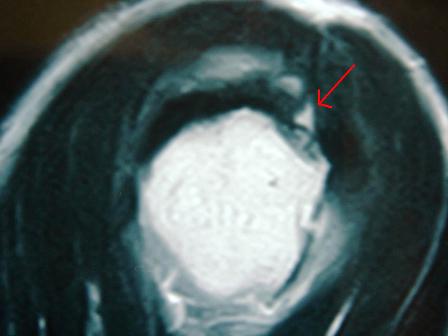

今はMRIで、ほんの小さな断裂も見つけられます。

図の矢印が断裂部分です。

腱板は肩甲骨の骨、肩峰(けんぽう)とぶつかって摩擦を繰り返すことで損傷が進みます。